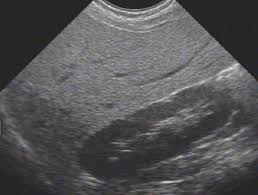

Değerlendirme (modern): LFT’ler (ALT/AST), GGT, lipid panel, HbA1c/OGTT, karın USG/Elastografi; inflamasyon/patoloji için CRP, ferritin, tiroid paneli.

Klinik çerçeve: Hastada insulin direnci + USG’de steatoz + TCM’de “Liver Qi Stagnation + Damp-Heat” tespiti varsa: